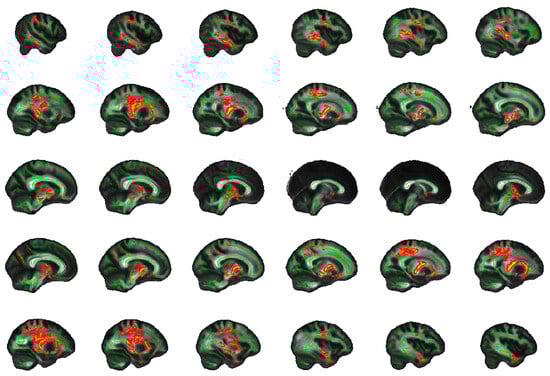

2.5. Exploratory Whole Brain Results

4.8. Exploratory Whole Brain Analysis

| Tracts | Side | Peak Voxel (MNI) | F-Statistic (TFCE) | Cluster Size > 100 (Voxels) | Cluster p-Value | ||

|---|---|---|---|---|---|---|---|

| x | y | z | |||||

| FA | |||||||

| SFOF | Left | −22 | −2 | 19 | 19.5 | 10,610 | 0.001 |

| ILF | Right | 45 | −11 | −27 | 14.2 | 6452 | 0.003 |

| UNC, IFOF | Right | 18 | 24 | −12 | 13.8 | 669 | 0.015 |

| AD | |||||||

| Unclassified | Left | −10 | −1 | −14 | 17.3 | 12,958 | 0.001 |

| ILF | Right | 40 | −22 | −21 | 11.5 | 1739 | 0.014 |

| Forceps minor | Right | 12 | 31 | 8 | 10 | 1522 | 0.028 |

| UNC, IFOF | Right | 28 | 14 | −10 | 9.84 | 786 | 0.03 |

| Unclassified | Right | 1 | 10 | 14 | 7.64 | 188 | 0.047 |

| Forceps minor | Left | −12 | 29 | −12 | 9.1 | 157 | 0.042 |

| SLF | Left | −34 | −37 | 21 | 10.3 | 141 | 0.038 |

| ATR, IFOF | Right | 23 | 26 | 23 | 5.94 | 141 | 0.047 |

| MD | |||||||

| ATR | Left | −11 | −17 | −2 | 18.1 | 31,113 | 0.001 |

| RD | |||||||

| ATR | Left | −23 | −2 | 17 | 18.8 | 14,709 | 0.001 |

| ILF | Right | 45 | −10 | −28 | 15.3 | 6641 | 0.004 |

| UNC, IFOF | Right | 18 | 24 | −12 | 13.4 | 209 | 0.039 |